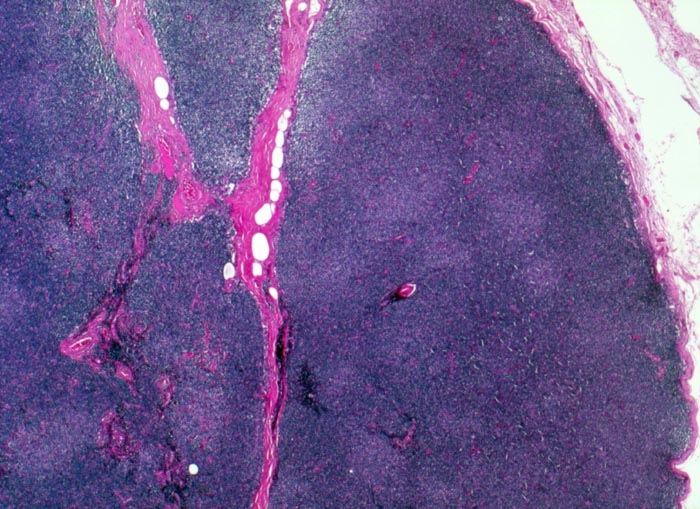

• Vergrösserter Lymphknoten mit zerstörter Lymphknotenarchitektur.

• Diffuse Infiltration des Lymphknotens durch monomorphe kleinlymphozytische Lymphomzellen.

• Unscharf begrenzte helle Areale (Proliferationszentren) auf dunkelblauem Hintergrund.

• Proliferationszentren (=Pseudofollikel) bestehend aus Lymphozyten und Paraimmunoblasten.

• Übergreifen des neoplastischen Infiltrates auf das umgebende Fettgewebe.